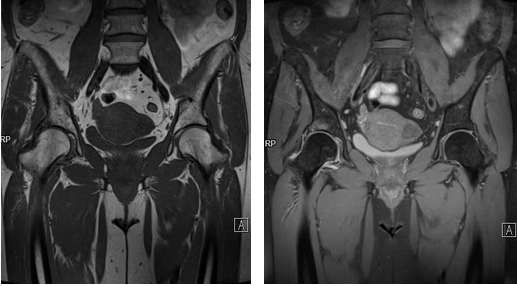

Первая из 34 аксиальных МР-томограмм таза, представленных сверху вниз. Отчетливо различимы три слоя мышц переднебоковой стенки живота. Поясничная мышца проходит книзу от своего многокомпонентного места прикрепления к позвоночнику. Наиболее верхний отдел подвздошного гребня соответствует уровню межпозвонкового диска L4/L5. Сразу ниже бифуркации аорты. Место соединения парной прямой мышцы живота в центре брюшной стенки посредством прочных фиброзных волокон называется белой линией. Средняя ягодичная мышца начинается выше других ягодичных мышц. Мышца, выпрямляющая позвоночник, представляет собой парный продольный мышечный комплекс, расположенный по задней поверхности позвоночника. Подвздошная мышца начинается широким основанием от глубокой поверхности подвздошной кости. Подвздошные артерия и вена проходят по медиальному краю поясничной мышцы, где артерия лежит кпереди от вены. Запирательный нерв на уровне пограничной линии проходит медиальнее поясничной мышцы. Нервный корешок L5 выходит из неврального отверстия. Подвздошные сосуды проходят вдоль медиальной поверхности поясничной мышцы. Обратите внимание, что подвздошная и поясничная мышцы разделены на большем протяжении своего пути через таз. Большая ягодичная мышца берет начало от наружной поверхности подвздошной кости позади средней ягодичной мышцы. Бедренный нерв проходит в подвздошно-поясничной вырезке. Запирательный нерв проходит позади поясничной мышцы. Поперечная и внутренняя косая мышцы живота имеют общее сухожилие/апоневроз. Наружная косая мышца более структурирована. Обратите внимание, что нервный корешок L5 проходит по передней поверхности крестца. На этом уровне крестцово-подвздошное сочленение представлено связками. Большая ягодичная мышца проходит книзу и кнаружи. В ее верхнем отделе визуализируется только небольшая мышечная порция. Комплекс мышцы, выпрямляющей позвоночник, книзу уменьшается в размере. Теперь визуализируется нервный корешок S2. На этом уровне определяется небольшой синовиальный крестцово-подвздошный сустав, однако большая часть сочленения образована мощными дорзальными связками. Из всех ягодичных мышц, малая имеет наиболее переднее начало. Передняя верхняя подвздошная ость визуализируется в качестве округлого расширения переднего отдела подвздошной кости. Здесь берут начало портняжная мышца и паховая связка. Связка представляет собой нижний край апоневроза наружной косой мышцы живота. Нервный корешок S1 покинул свое отверстие и проходит вниз и кнаружи, в то время как корешок S2 все еще находится в пределах отверстия. Подвздошная и поясничная мышцы более плотно прилежат друг к другу, оставляя, однако, небольшую вырезку между собой, в которой проходит бедренный нерв. Подвздошная и поясничная мышцы на этом срезе плотно прилежат друг к другу, однако подвздошно-поясничная борозда между ними, в которой проходит бедренный нерв, остается хорошо различимой. Подвздошные сосуды разделились надвое. Внутренние подвздошные сосуды проходят кзади, пересекая таз. Крестцово-подвздошное сочленение представлено синовиальным суставом в его наиболее нижнем отделе. Дорзальные крестцово-подвздошные связки визуализируются кзади от синовиального сустава и являются важными стабилизаторами таза. Верхние ягодичные сосуды на этом срезе отделены от внутренних подвздошных сосудов. Наружные подвздошные сосуды сохраняют свое положение вдоль медиальной поверхности поясничной мышцы. Подвздошная и поясничная мышцы имеют собственные точки прикрепления, однако от этого уровня и ниже их называют подвздошно-поясничной мышцей. Запирательный нерв визуализируется по медиальному краю поясничной мышцы кзади от наружных подвздошных сосудов. Верхние ягодичные сосуды покидают полость таза вдоль верхнего края грушевидной мышцы. Внутренняя косая и поперечная мышцы живота здесь расположены медиальнее, чем на более верхних срезах. Такое расположение соответствует их нижнемедиальной направленности. На этом срезе различимы мышечные волокна напрягателя широкой фасции. Задняя нижняя подвздошная ость является ориентиром передне-верхнего края большой седалищной вырезки. Ветви внутренних подвздошных сосудов и нервных корешков крестцового сплетения находятся в сложном взаимоотношении на глубокой поверхности грушевидной мышцы. После того как верхние ягодичные сосуды покидают таз они проходят в жировой ткани под большой ягодичной мышцей. Грушевидная мышца берет начало от крестца, проходит кнаружи через большую седалищную вырезку в сопровождении седалищного нерва по его переднему краю. На этом срезе визуализируется портняжная мышца ниже места своего начала от передней верхней подвздошной ости. Передняя нижняя подвздошная ость расположена непосредственно выше вертлужной впадины. Эта ость является местом начала передней головки прямой мышцы бедра, а подвздошно-бедренная связка берет начало от ее нижнего края. Портняжная мышца расположена кпереди от поясничной мышцы. Сухожилие передней головки прямой мышцы бедра представляет собой узкую структуру, расположенную латеральнее подвздошно-поясничной мышцы. Нижняя часть наиболее медиальной порции поперечной мышцы живота и внутренняя косая мышца живота формируют общее сухожилие. Ниже этого уровня сухожилия неотличимы от прямой мышцы живота. Внутренние половые сосуды расположены кзади от запирательного нерва. Визуализируется крестцово-остистая связка. Она лежит кпереди от крестцово-бугорной связки. Подвздошно-поясничная мышца вплотную прилежит к переднему отделу тазобедренного сустава непосредственно латеральнее бедренных артерии и вены. Седалищный нерв покинул большую седалищную вырезку и лежит позади вертлужной впадины. Паховая связка расположена непосредственно кнаружи от прямой мышцы живота. Как и мышцы, эта структура направлена косо вниз и медиально, поэтому здесь мы можем видеть только ее часть, а более нижний отдел расположен медиальнее. Вдоль глубокой поверхности большой ягодичной мышцы сегментарно визуализируется крестцово-бугорная связка. Вертикальное расположение этой связки означает то, что на аксиальной томограмме она будет визуализироваться лишь сегментами. К этому уровню наружные подвздошные сосуды пересекли паховую связку снизу и стали общими бедренными сосудами. Вена лежит медиальнее артерии, а бедренный нерв—латеральнее от нее. Обратите внимание на резкую перемену направления внутренней запирательной мышцы после ее выхода из таза, когда она огибает задний край вертлужной впадины. Седалищный нерв тесно прилежит к задней поверхности сухожилия внутренней запирательной мышцы и его сложно идентифицировать. Прямые мышцы живота приближаются к месту своего начала на гребне лобковой кости. Обратите внимание на ответвления сухожилия прямой мышцы живота вдоль передней поверхности лонного сочленения, сливающиеся с приводящим апоневрозом, который непрерывно связан с началом длинной приводящей мышцы. На этом срезе визуализируются приводящие мышцы бедра. Наиболее высоко расположена гребенчатая мышца. Внутренняя запирательная мышца в просвете запирательного отверстия полностью закрывает внутреннюю поверхность. Седалищный нерв расположен латеральнее вертлужной впадины и проходит вдоль глубокой поверхности большой ягодичной мышцы.